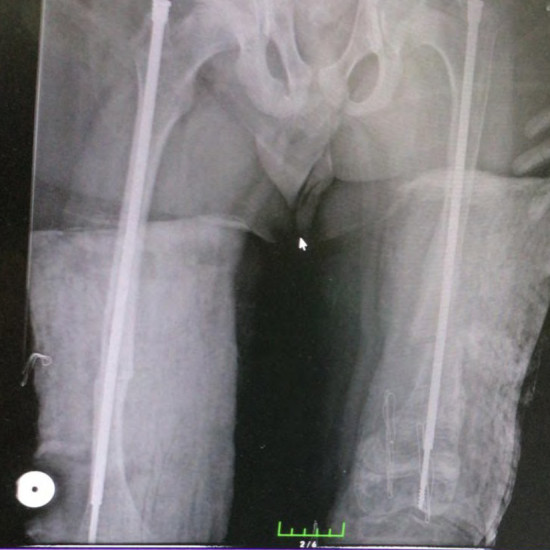

Telescopic Nail